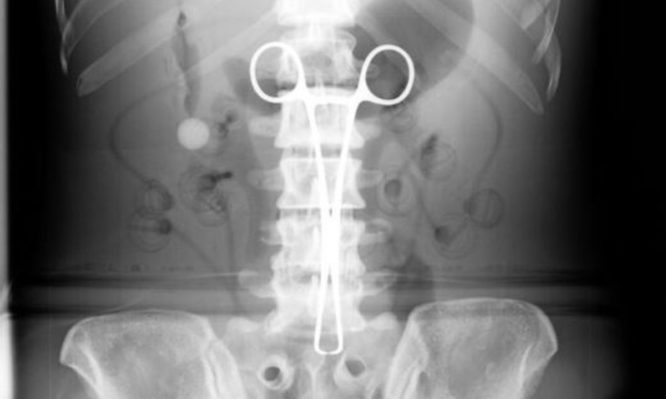

Είχαν ξεχάσει χειρουργική λαβίδα στην κοιλιά του από το… 1998!

Γιατροί στο Βιετνάμ αφαίρεσαν μία χειρουργική λαβίδα από το σώμα ενός άνδρα όπου βρισκόταν χωρίς αυτός να το έχει...